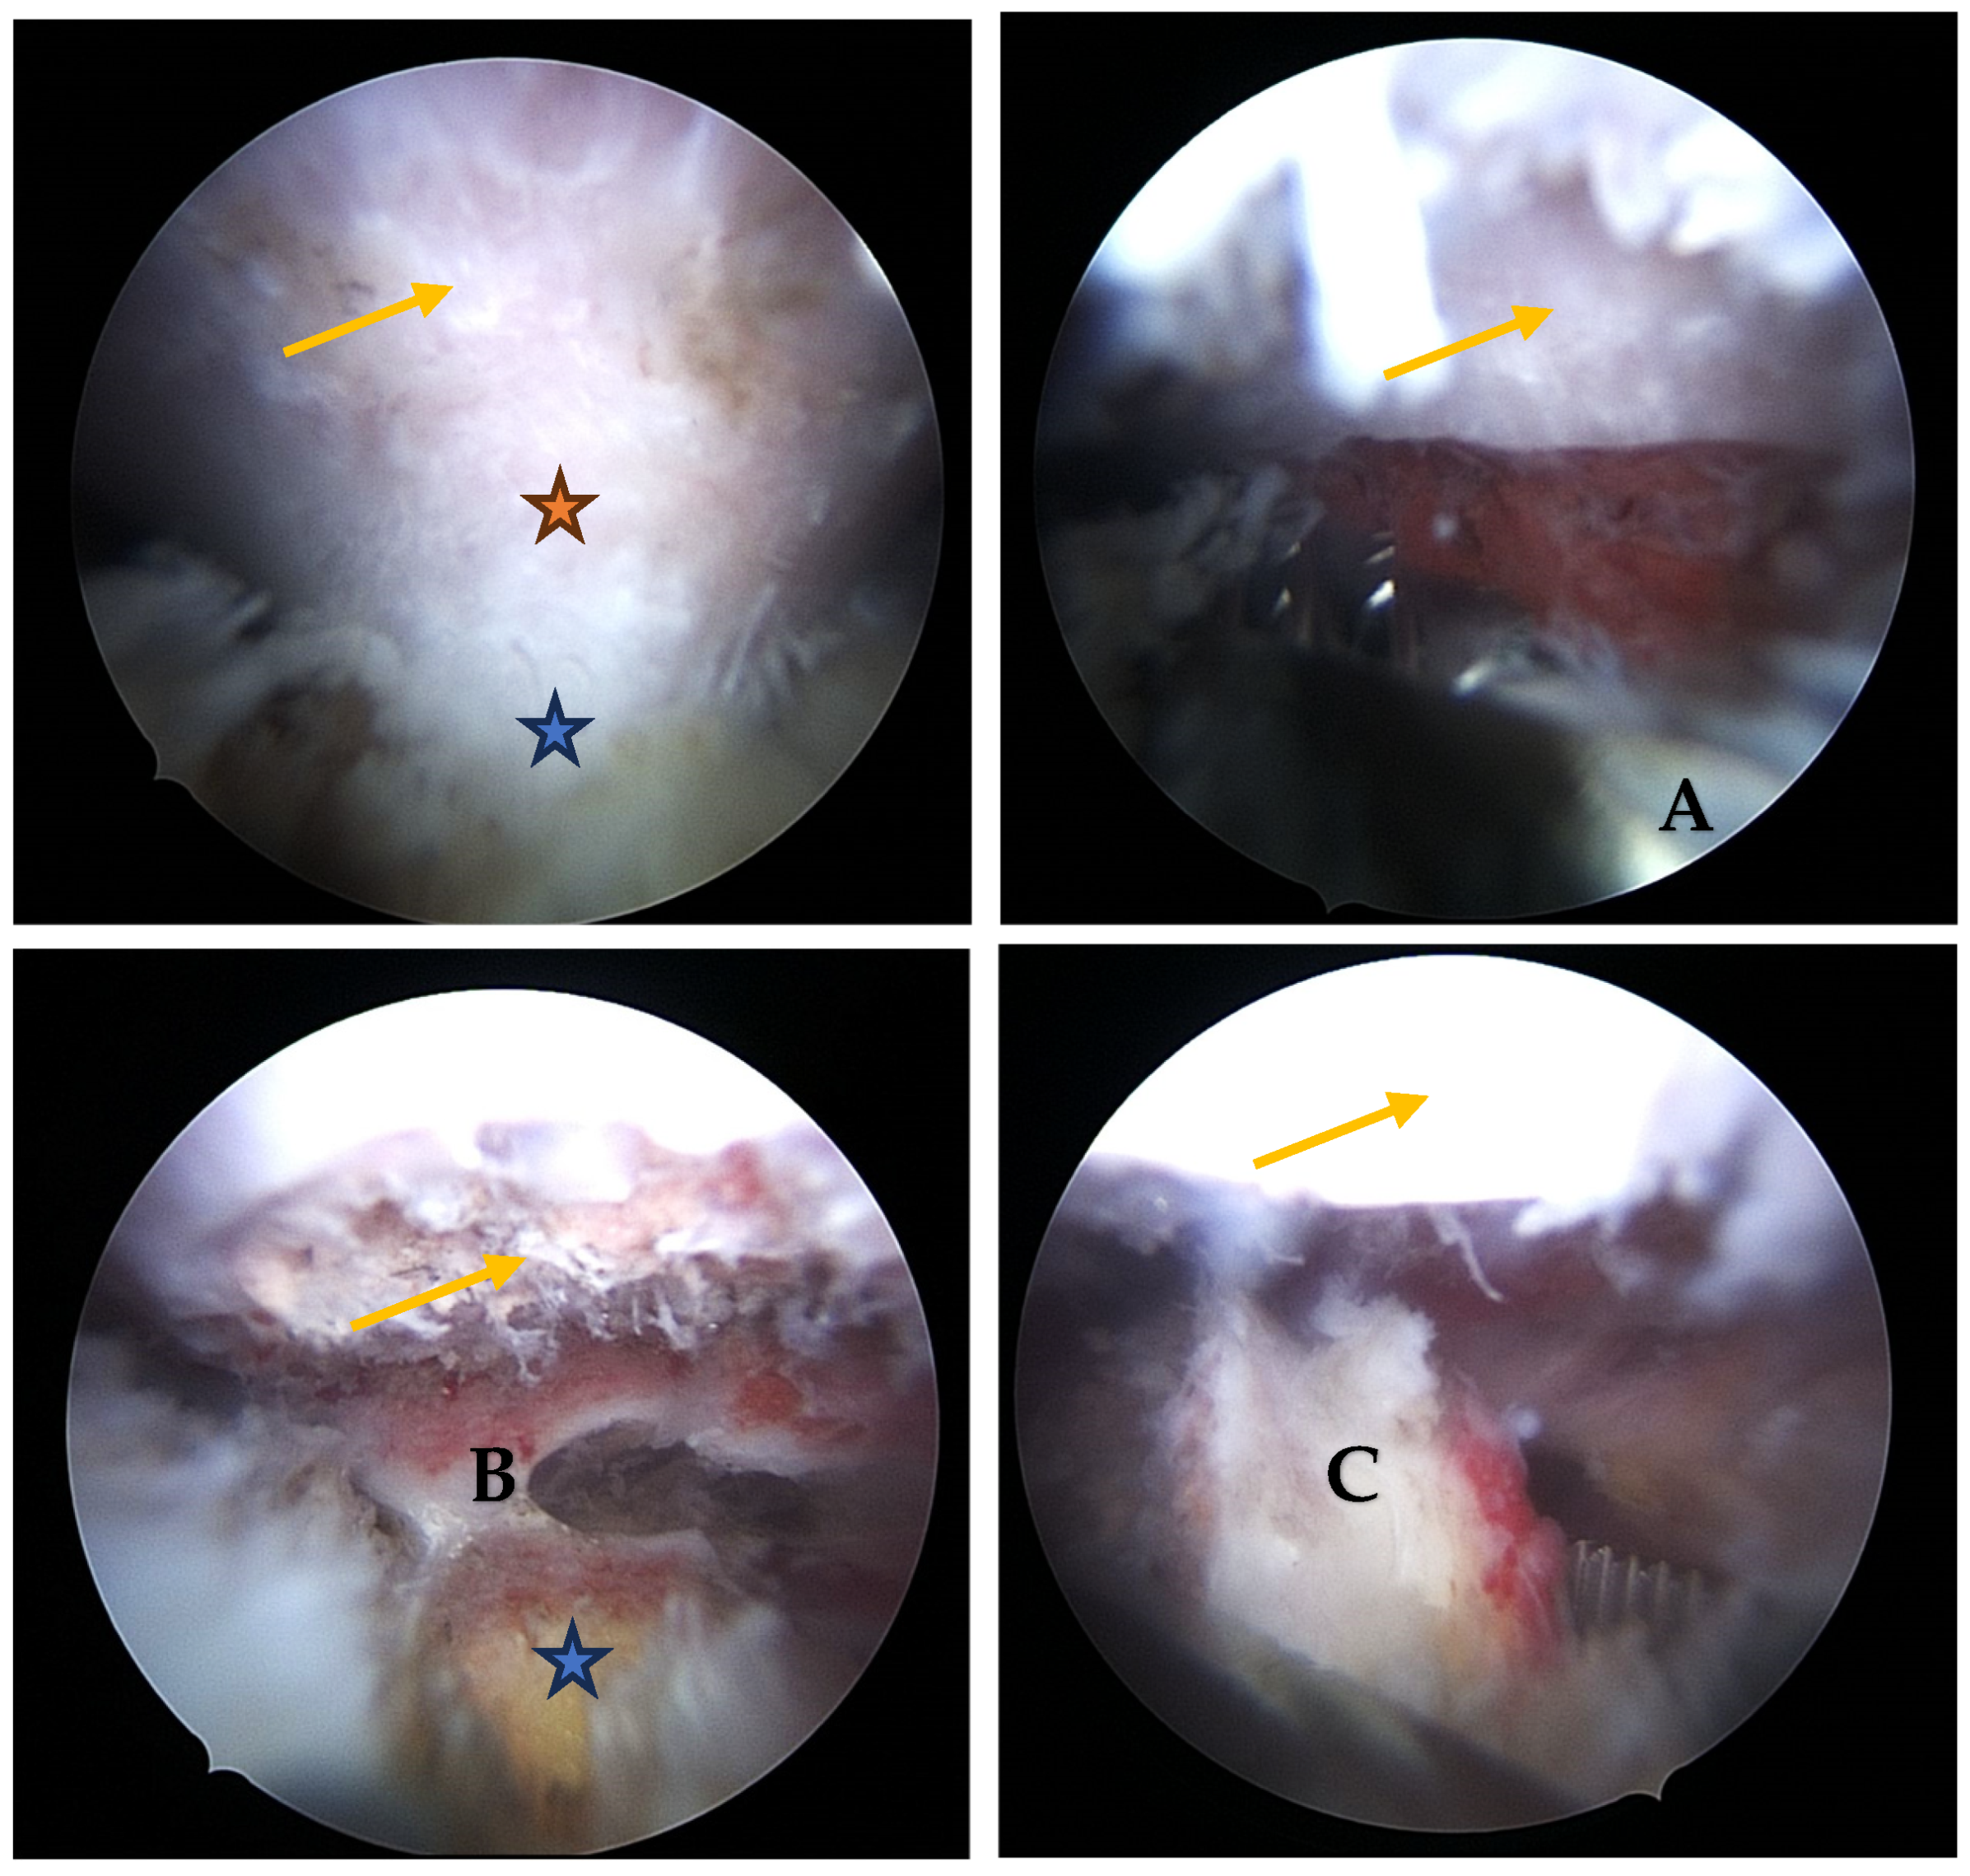

- Visualization: The arthroscope is introduced through the posterior portal. Initial visualization targets the inflamed scapulothoracic bursa to gain orientation (Figure 3A,B). In the present case, the exostosis was partially protruding through the subscapularis muscle and thus visible upon entry. A blunt dissection plane is established between the scapula and the subscapularis muscle to expose the exostosis base.

- Resection: Using a high-speed burr under continuous irrigation, the lesion is carefully resected flush to the scapular surface. To ensure oncologic safety, the exostosis is excised at its base as a single piece and removed using an arthroscopic grasper for histopathological examination (Figure 4). Constant visualization is maintained to avoid iatrogenic injury to adjacent structures.

- Histopathological Confirmation: The excised specimen (Figure 5) is sent for formal pathological analysis. In our case, the diagnosis of benign osteochondroma was confirmed without atypical or malignant features.

- Hemostasis and Debridement: Electrocautery (vapor electrode) is used to control minor bleeding. Loose bone fragments and inflamed bursal tissue are debrided thoroughly using a 4 mm shaver and suction.